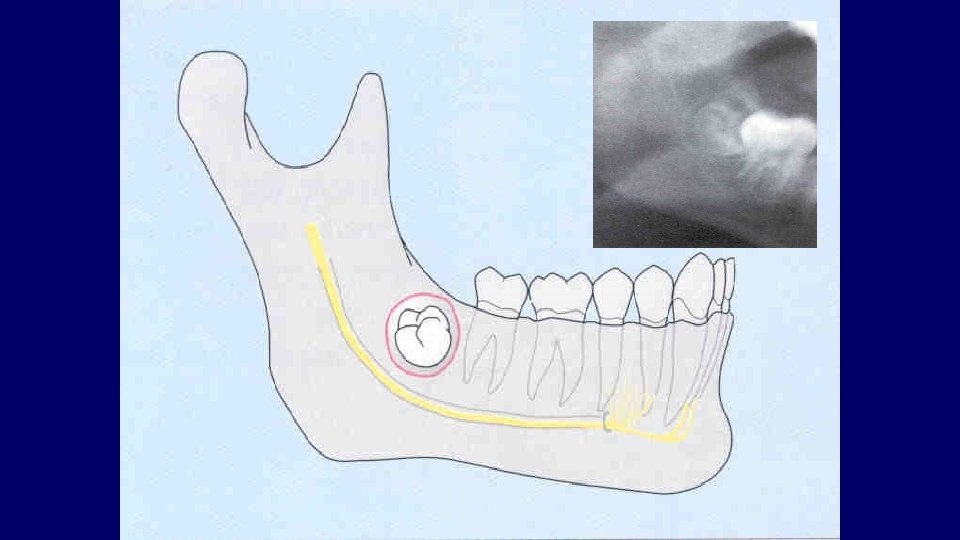

Types of impaction • Vertical • Mesioangular • Distoangular • Horizontal • Transverse

(2) Depth of impaction

Pell & Gregory Classification • Based on the amount of tooth covered by the anterior border of the ramus • The depth of the impaction relative to the adjacent tooth

Pell & Gregory • Depth of Impaction – Mandibular Class A Class B Class C

Pell & Gregory